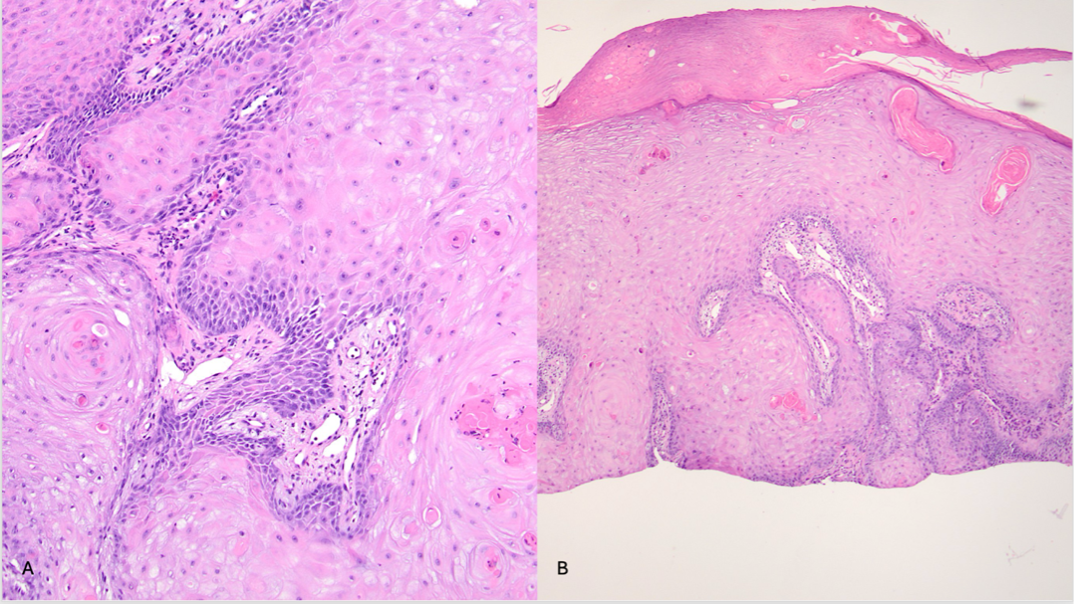

Diagnostic testing. A biopsy of a nodule on the right forearm revealed keratinocytes with ample glassy cytoplasm extending into the dermis, nuclear pleomorphism, and neoplastic keratinocytes extending to the resection margin (Figure 2A and B). These findings supported a diagnosis of squamous cell carcinoma of the keratoacanthomatous type.

Figure 2A-B. The specimen reveals keratinocytes with ample glassy cytoplasm extending into the dermis. (A) Nuclear pleomorphism is encountered, with neoplastic keratinocytes extending to the margin of the resection. (B) The architecture favors a diagnosis of a squamous cell carcinoma of keratoacanthomatous type.